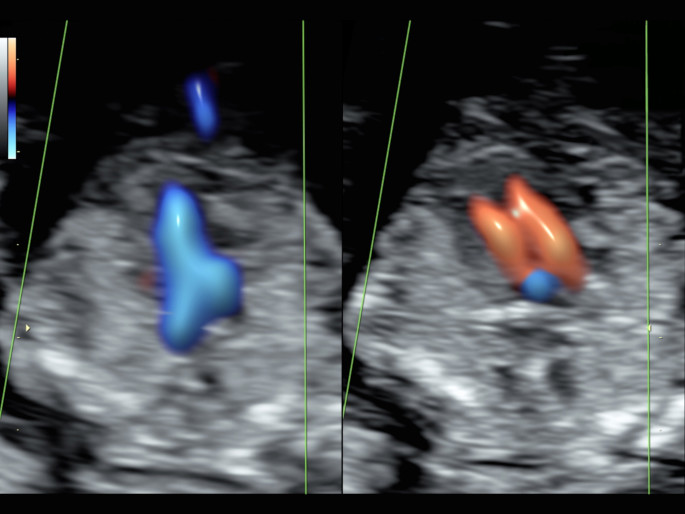

Die fetale Echokardiographie dient der vorgeburtlichen Erkennung von angeborenen Fehlbildungen des Herzens:

Herzfehler zählen zu den häufigsten angeborenen Fehlbildungen und eine frühzeitige Diagnosestellung ermöglicht es, die weitere Überwachung der Schwangerschaft, Geburt und anschließende Versorgung optimal zu organisieren.

Hierbei werden Größe und Lage des Herzens, die Herzkammern und- klappen sowie die zum Herzen führenden und abgehenden großen Gefäßen und Venen beurteilt. Durch Ultraschalltechniken wie Farbdoppler, gepulster Doppler, M-Mode und 3D-Techniken (STIC) können ca. 85% aller angeborenen Herzfehlerentdeckt werden.